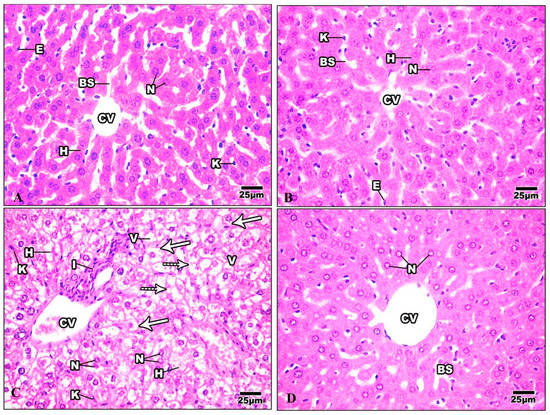

3.3.1. Liver

3.3.2. Kidney